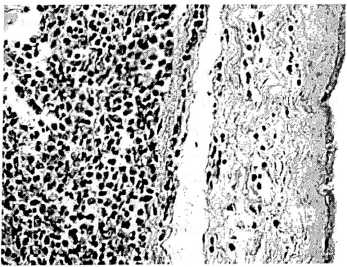

Рис. 1. Диффузный гнойный хориодецидуит с начальными признаками амнионита. Диффузная лейкоцитарная инфильтрация трофобластического и децидуального слоев плодной оболочки, незначительная лейкоцитарная инфильтрация амниотической оболочки. Окраска гематоксилином и эозином, х 350.

Гистологические признаки воспаления, возникающие при поражении тканей последа различными условно-патогенными микробами оказались весьма сходными. Этим было обусловлено суммарное описание выявленных изменений. Патоморфологическая картина хориоамнионита характеризовалась преимущественно диффузной инфильтрацией полиморфноядерными лейкоцитами ткани плаценты и плодных оболочек (рис. 1,2), а в некоторых случаях участками некрозов и микроабсцессов (рис. 3,4). Чаще всего воспалительные инфильтраты локализовались в хориальной пластинке, базальной пластинке, амнионе, периваскулярном отделе стромы крупных ворсин и интервелезном пространстве. Наряду с воспалительными изменениями в 36,3% наблюдений отмечены инволютивно-дистрофические и дисциркуляторные нарушения.